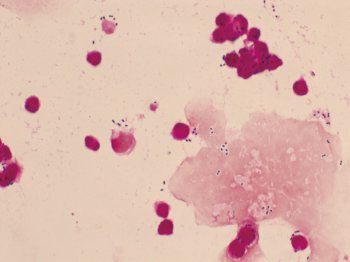

肺炎球菌性髄膜炎患者の髄液 Gram染色(×1000)